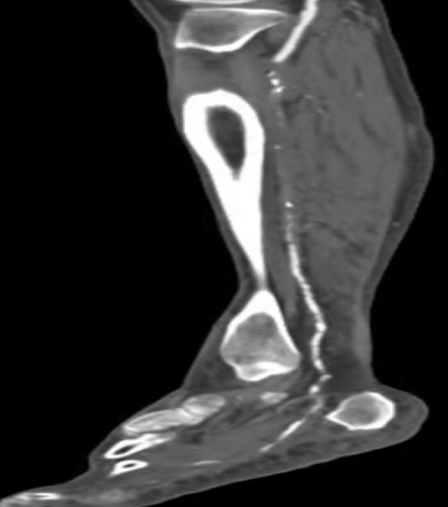

下肢動脈CTA

情急之下去了當(dāng)?shù)蒯t(yī)院,醫(yī)生一瞧告訴王大伯:“您這可能是糖尿病足,你這傷口肯定是長不好了,需要外科手術(shù)清創(chuàng)、植皮,如果還是長不好就要截肢”。聽了醫(yī)生的話,王大伯出了一身冷汗,幾經(jīng)周折最終來到了我院血液內(nèi)分泌科,住院后進(jìn)行下肢動脈超聲及CTA發(fā)現(xiàn):雙下肢膝下動脈節(jié)段性狹窄、閉塞。診斷為:右下肢動脈硬化閉塞癥(Runtherford6級),糖尿病下肢嚴(yán)重缺血(右側(cè)),右足潰瘍;經(jīng)多學(xué)科會診初期"改善循環(huán)、控制血糖、抗感染、局部清創(chuàng)換藥、營養(yǎng)神經(jīng)、支持治療"六環(huán)法措施下,老伯潰瘍雖有好轉(zhuǎn),但仍不能完全愈合,右足仍靜息下疼痛。